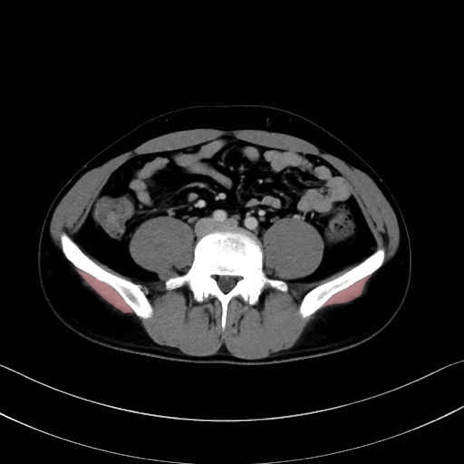

中殿筋 (Gluteus medius)